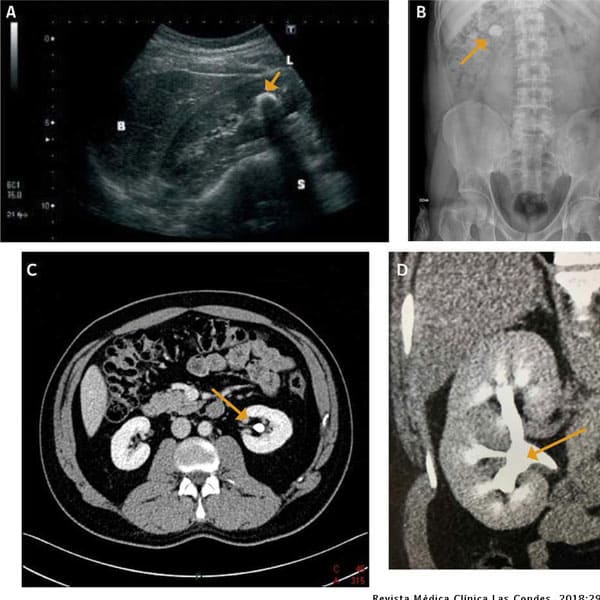

Realización de ultrasonido renal

Es un examen seguro y sin dolor el cual permite al nefrólogo ver imágenes de los riñones y la vía urinaria.